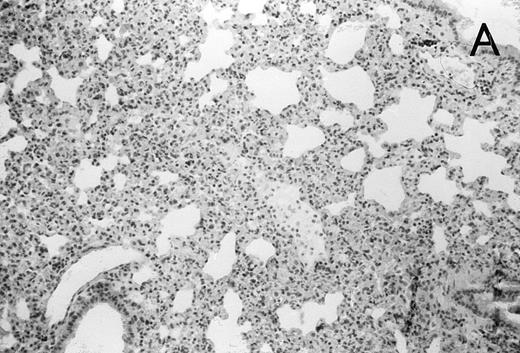

Histology further supported this observation. Control animals showed well-developed pneumonia with abscess formation (Fig3A) in their lungs, but in their livers, only small areas of inflammation with scattered microabscesses and foci of hepatic necrosis were observed (Fig 3B). In contrast, mice pretreated with G-CSF had only mild peribronchitic alterations in their lungs without signs of containment of inflammation such as abscess formation (Fig 4A). Livers and spleens of mice pretreated with G-CSF were severely altered, showing large abscesses which contained massive amounts of bacteria (Fig 4B). In addition, large necrotic areas surrounded by granulocytes were observed in the livers (Fig 4C). When MoAb III/5-1 was administered in addition to pretreatment with G-CSF, almost all changes observed in animals pretreated with G-CSF were reversed: there were only minor bronchial and peribronchial infiltrations by granulocytes (minimal change focal pneumonia), and the livers showed small microabscesses as observed in control mice. When treatment with G-CSF was started at 24 hours after bacterial challenge, a mixed pattern was observed. In the lungs, there was a beginning pneumonic reaction and a moderate perivascular and septal edema. However, in the liver there was almost no difference to the severe alterations observed in mice pretreated with G-CSF: huge abscesses loaded with bacteria joined extended necrotic areas.

(A) Micrograph of lung tissue 72 hours after intranasal infection with 1 × 103 CFU of K pneumoniae B5055. Lung abscess with severe tissue destruction in a PBS-treated control animal. Hematoxylin & Eosin (H&E); original magnification ×150. (B) Small foci of hepatic necrosis. H&E; original magnification ×600.

(A) Micrograph of lung tissue 48 hours after intranasal infection with 1 × 103 CFU of K pneumoniae B5055 and pretreatment with G-CSF (50 μg/kg sc) at −48 hours, −36 hours, −24 hours, and −12 hours before infection. Peribronchiolar neutrophils without destruction of lung parenchyma. H&E; original magnification ×150. (B) Splenic abscesses in the red pulp containing numerous gram-negative bacilli are found. H&E; original magnification ×370. (C) Confluent hepatic necroses. H&E; original magnification ×150.